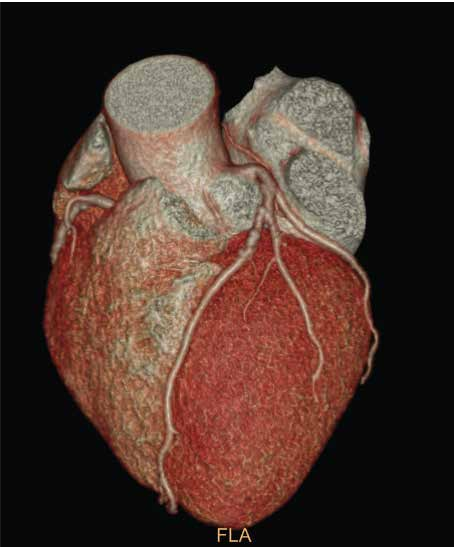

同类CT中的佼佼者,扫描1周仅需0.35秒,旋转一圈可以获得128层图像,5秒内完成无创心脏检查,10秒内完成全身检查,且每次扫描辐射剂量及低。冠状动脉CTA使无创冠脉检查成为现实:短短数秒之内便可得到清晰,准确的冠脉影像,快速无创的诊断冠脉狭窄、斑块等病变。这意味着患者在受到尽可能少的辐射暴露的同时,医生也能迅速获取高质量的影像资料,从而加快诊断流程,为及时治疗赢得宝贵时间。

▲ 冠脉CTA:血管病变清晰可见